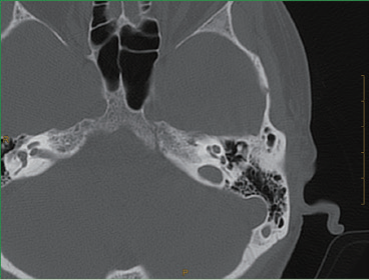

The precise tomographic technique

The thickness of the precision tomography images is only 0.275mm, both the inner ear structures such as the

ossicles and the cochlea, and the relationship between the inner ear structures are clearly visible, such as the

connection of the malleus and the corpora incudis.

The conventional tomographic inner ear image